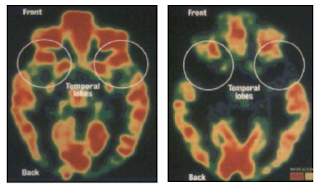

ครูในประเทศไทยในปัจจุบันมักจะมีข่าวที่เกี่ยวกับครูทำร้ายนักเรียบ่อยๆ ซึ่งมันไม่ค่อยดีต่อตัวนักเรียนนัก แล้วอะไรมันเป็นเหตุจูงใจที่ทำให้คุณครูทำกับเด็กแบบนั้นสาเหตุมันก็มาจากการที่มองว่าการลงโทษนั้นไม่รุนแรงจนเกินไป ด้วยสาเหตุนี้แหละครับทำให้ครูบางส่วนนั้นลงมือทำอะไรลงไปไม่ว่าแรงหรือไม่ร้ายแรง เป็นสิ่งที่ยอมรับได้ และทำไปเพื่อควบคุมนักเรียนให้อยู่ในโอวาทครับ แต่ว่าผลที่ตามมานั้นมันไม่ได้จบในการกระทำของคุณครูแค่ครั้งเดียวแน่นนอน เพราะว่าผลที่ตามมาอาจจะส่งผลไปถึงสภาพทางร่างกายและจิตใจอย่างแน่นอน ถ้าหากเป็นทางร่างกายก็อาจจะทำให้เจ็บ แต่แป็บเดียวมันก็หาย ถ้าหากเป็นทางจิตใจแล้วหละก็มีการศึกษาความรุนแรงที่กระทำต่อเด็กโดยมีผลออกมาว่าเมื่อเกิดความความเครียดแบบรุนแรง สมองก็จะหลั่งฮอร์โมนที่มีชื่อว่าคอร์ติซอล (Cortisol) ซึ่งก็จะหลั่งออกมาในปริมาณมาก ซึ่งมันก็จะไปปิดกั้นกระบวนการพัฒนาทางสมอง โดยมันจะส่งผลโดยตรงต่อพฤติกรรมของเด็ก